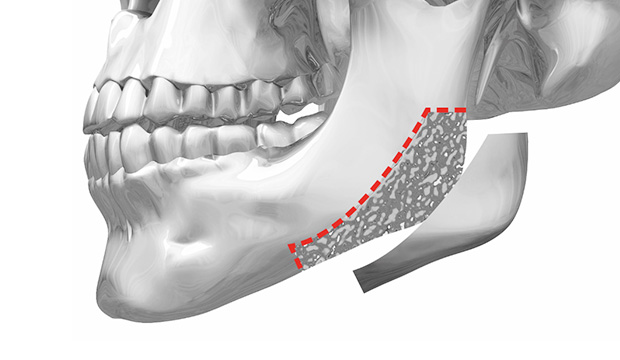

01. 皮質切除術

正面線條的卓越改善效果

WIAD方下巴縮小術透過將皮質整體切除(full thickness corticectomy),實現最卓越的正面改善效果。

皮質切除術

皮質切除術可以明顯縮小從正面看不見部位的線條。